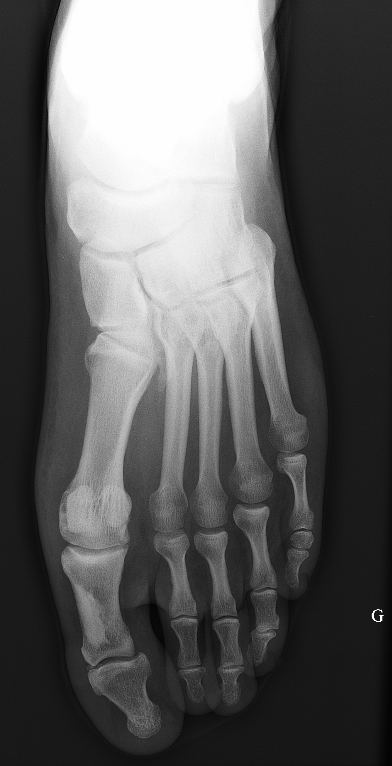

Le cas : Mr.S., 32 ans, consulte aux urgences pour douleurs du pied gauche en inversion forcée. A l’examen on note une douleur de la base du 5ème métatarsien à la palpation et à l’éversion contrariée. La malléole latérale est indolore. Il n’existe pas de douleur à la mobilisation de la transverse du tarse. La marche est difficile. Devant ces signes cliniques, vous demandez un bilan radiographique. Vous êtes attiré par une image radiologique qui semble sans rapport avec ce traumatisme. Voici une partie des images que vous obtenez:

Mr.S., 32 ans, consulte aux urgences pour douleurs du pied gauche en inversion forcée. A l’examen on note une douleur de la base du 5ème métatarsien à la palpation et à l’éversion contrariée. La malléole latérale est indolore. Il n’existe pas de douleur à la mobilisation de la transverse du tarse. La marche est difficile. Devant ces signes cliniques, vous demandez un bilan radiographique. Vous êtes attiré par une image radiologique qui semble sans rapport avec ce traumatisme. Voici une partie des images que vous obtenez:

Rx pied

Sur ce cliché de pied, on objective une opacité située sur le bord médial (interne) de la première phalange de l’hallux, « appendue » à corticale médiale. Il n’y a aucune déformation de la corticale ni d’image lacunaire (ce qui écarte une tumeur osseuse primitive maligne et un ostéochondrome). Cette opacité est homogène, sans clarté centrale ni aspect piqueté. Cette image n’est pas arrondie, elle ressemble plutôt à une coulée de bougie. Il s’agit d’une image de mélorhéostose.

Une condensation osseuse en coulée de bougie doit faire évoquer une mélorhéostose.